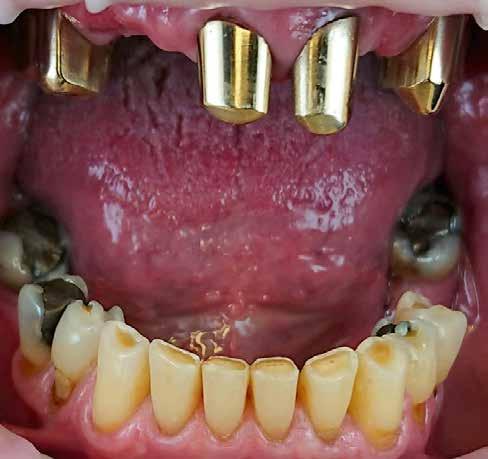

Az már egyértelművé vált, hogy a fogászati CAD/CAM, a folyamatos, gyors fejlődésének köszönhetően évről évre nagyobb részt fed le a kézműves, manuális fogtechnikai munkafolyamatok területén. A 3D nyomtatás fejlesztése, a szoftveres alkalmazások bővítése ma már lehetővé teszi digitálisan készített kivehető pótlások készítését. Teljes alsó-felső protézis vagy éppen fémlemez már kivitelezhető CAD/CAM technológiával. A fémlemezes részleges kivehető megoldások teljes digitális megoldásai még váratnak magukra, de ne legyenek illúzióink (1. kép).